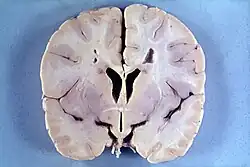

Neuropatologia da doença de Alexander. Na imagem, podemos observar um cérebro de um rapaz de 4 anos que possui macrocefalia e desmielinização periventricular (a descoloração acastanhada à volta dos ventrículos cerebrais).